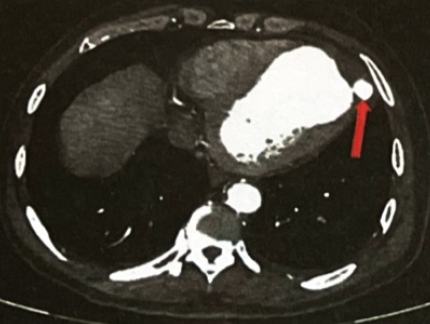

超声心动图示左心扩大,左心室节段性室壁运动异常,左心室心尖部真性室壁瘤形成,左心室心尖假性室壁瘤并血栓填充,升主动脉增宽,室间隔、左心室璧明显增厚,左心收缩功能减低,心包腔少量积液(LVEDD 6.3 cm,LVEF 38%)(图3)。

图3. 左心声学造影

冠状动脉CTA示左心室心尖部真性室壁瘤,大小约65 mmx53 mm;真性室壁瘤破溃,外凸形成血肿,内有血栓形成,假性室壁瘤大小55 mmx38 mm,血栓大小44 mmx24 mm(图4)。